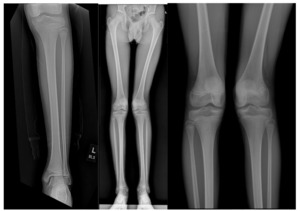

As the pain persisted, a follow-up appointment with orthopedic surgery was scheduled. By this time, the pain had been continuous for seven weeks. A review of imaging as well as further radiographs of the lower extremity revealed a left genu valgum, a minor limb length discrepancy, and a potential distal lateral femur physis bar [Figures 1a, 1b, 1c].

The patient’s mother reported that he had a left knee infection at 1.5 years old which was managed operatively. She was however unsure if this infection was septic arthritis or osteomyelitis. As his genu valgum may have been related to bony changes following the infection, further imaging was ordered. A left knee CT scan and MRI showed a distal lateral femur physis bar measuring 1.1 x 0.8 cm in the transverse and antero-posterior dimensions respectively.